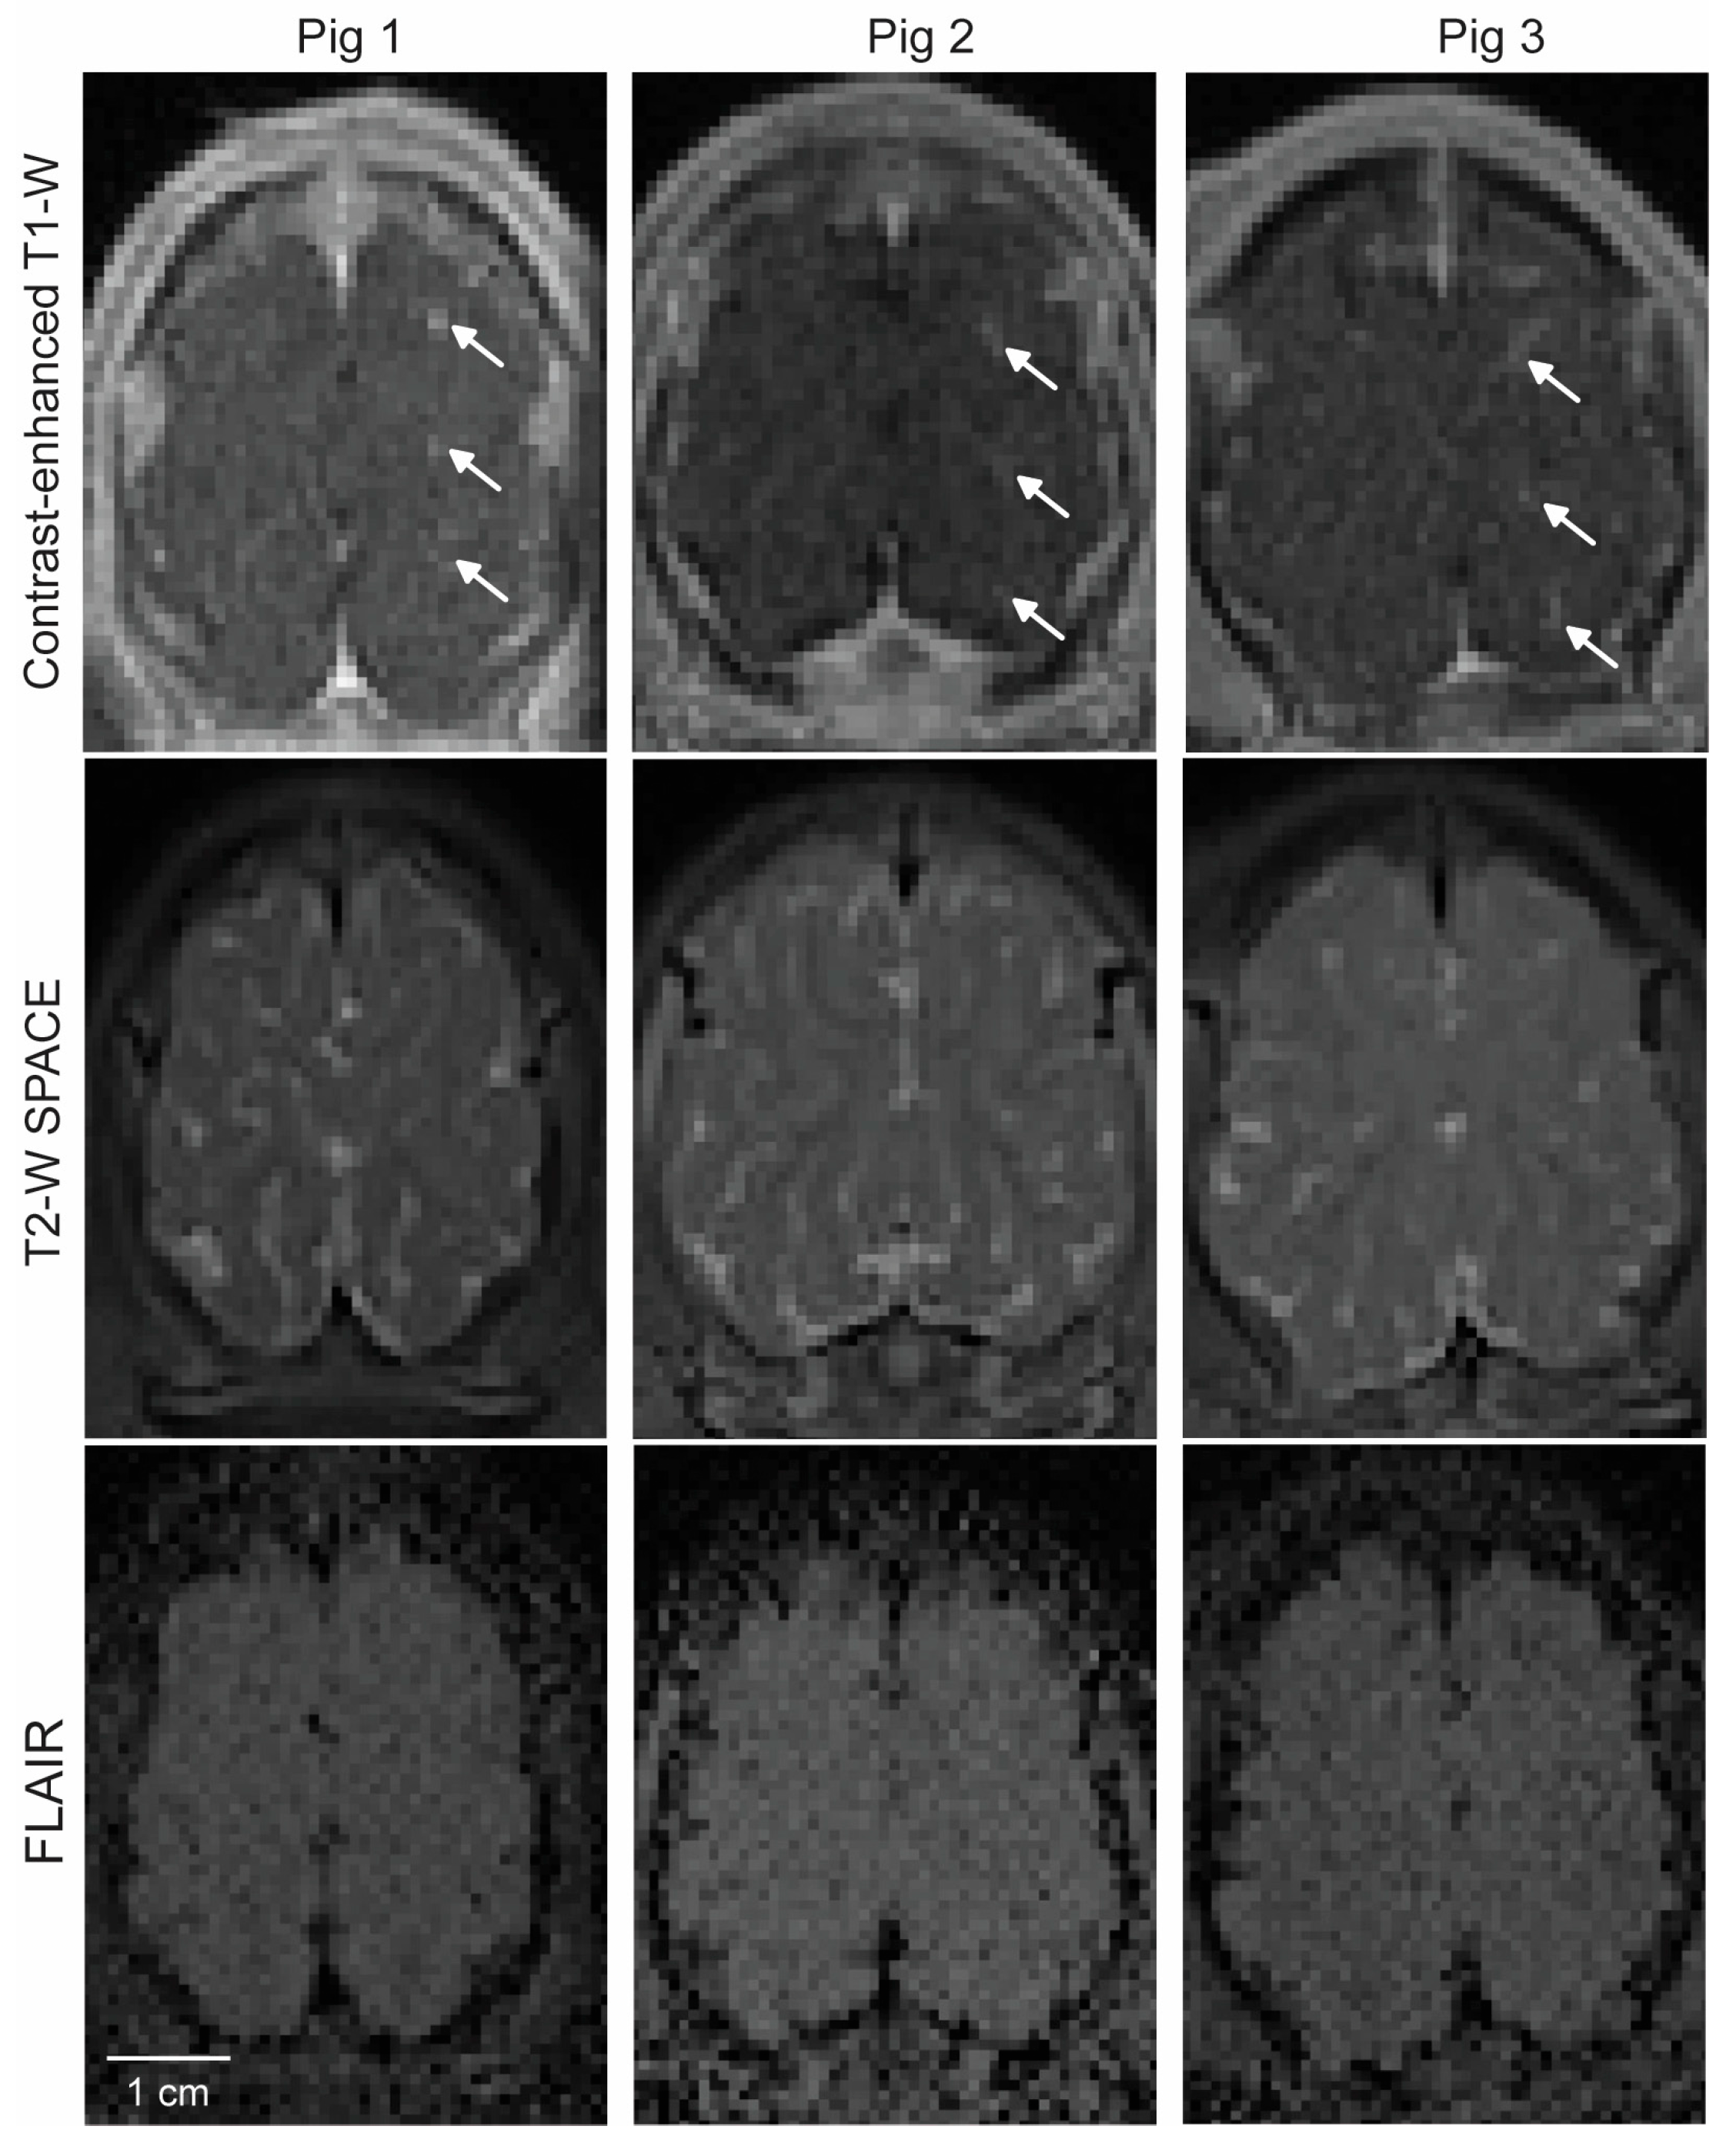

3.1. MRI Confirmation of FUS-BBBO